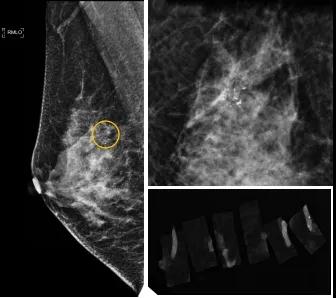

小到1—2mm的鈣化也能活檢!西安國際醫(yī)學(xué)中心醫(yī)院采用精準(zhǔn)技術(shù)讓乳腺早癌無處可逃

46歲的某女士在西安國際醫(yī)學(xué)中心醫(yī)院體檢時,行乳腺X線攝影(俗稱鉬靶)發(fā)現(xiàn)右乳可疑簇狀鈣化,分布范圍不到1厘米,臨床觸不到,超聲很難發(fā)現(xiàn),但是這種鈣化風(fēng)險比較高,依據(jù)國際BI-RADS指南需要明確病理!

西安國際醫(yī)學(xué)中心醫(yī)院影像診療中心陳寶瑩副主任帶領(lǐng)的團(tuán)隊,采用全數(shù)字化乳腺X線三維立體定位系統(tǒng)可實施。這個團(tuán)隊的成員大部分來自知名三甲醫(yī)院,有著十余年影像引導(dǎo)下乳腺介入診療的經(jīng)驗,X線引導(dǎo)穿刺定位和活檢例數(shù)居西北前列。為減少患者創(chuàng)傷,在詳細(xì)判讀了患者資料,并與患者及甲乳外科劉曉敏主任充分溝通的基礎(chǔ)上,團(tuán)隊確定采用全數(shù)字化乳腺X線三維立體定位系統(tǒng)下實施粗針活檢。

當(dāng)天,乳腺X線三維立體定位系統(tǒng)清晰顯示出了所有鈣化。為了獲取充足的組織量,保證病理診斷的準(zhǔn)確性,團(tuán)隊選用14G穿刺針并多點、多角度取材,組織取出后,又立即在高清標(biāo)本攝影系統(tǒng)中進(jìn)行投照,從而確定了取出組織中具有足夠的可疑鈣化。整個過程患者無任何不適,活檢結(jié)束后即回家觀察。